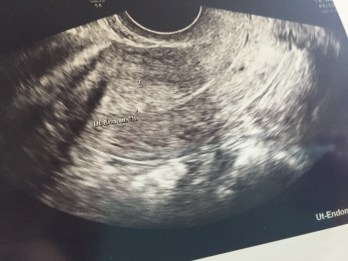

We’re not quite ready yet. We went to the doctor for our scheduled ultrasound and my lining isn’t at the thickness they’d like it to be. It’s almost there, just not where it needs to be. So our transfer is pushed back one week. Dr. Huang said this is normal and nothing to worry about!